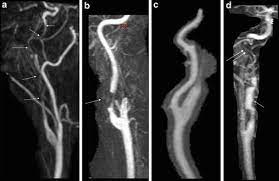

Carotid artery dissection (concept id: Each common carotid artery has an internal and an external branch. Carotid artery dissection is a tear in one of the layers of the artery wall. Spontaneous dissection of the carotid artery occurs in 3 per 100,000 of the population annually (1). It manifests with headache, neck pain, temporary vision loss, and/or ischemic stroke. This causes bleeding into the artery wall. Commonest in those in their mid 40s but seen at any age. Roller coasters are also a no no. Blood vessel walls normally have three layers, and a tear in any of these can allow blood to flow into the resulting space, causing the vessel to bulge. The first portion of each carotid artery is the called the common carotid artery. Carotid artery dissection is a major cause of cerebral infarction in the young. Mr signal of the mural hematoma has a similar temporal evolution than intracerebral counterpart. A carotid dissection can be due to injury.

The natural history of cerebrovascular fmd is unknown and management of symptomatic patients can be challenging. A carotid dissection is a tear in the inner layer of the wall of a carotid artery that allows bleeding into the artery wall. Internal carotid artery (ica) dissection, like arterial dissection elsewhere, is a result of blood entering the media through a tear in the intima 1 and is a common cause of stroke in younger patients. Carotid artery dissection has been described after chiropractic manipulation. It can involve a carotid or vertebral artery and sometimes multiple arteries can be involved.

Arterial dissection is a tear of the inside of the artery. The tear that initiates the dissection may occur spontaneously or after injury. Medical imaging tests can help rule out other conditions with similar symptoms. The first portion of each carotid artery is the called the common carotid artery. These arteries supply blood to your brain. May occur spontaneously, or in the setting of major/minor neck trauma (mvc (classically a seat belt injury)) vs. Similarly, dissections affect distal parts of the extracranial vertebral artery, whereas atherosclerosis tends to involve the proximal segments C0338585) spontaneous or traumatic separation of the layers of the carotid artery wall. Carotid dissection is a tear in the carotid artery wall. But it's still a dangerous situation. I will elaborate in a few sentences. Blood vessel walls normally have three layers, and a tear in any of these can allow blood to flow into the resulting space, causing the vessel to bulge. It manifests with headache, neck pain, temporary vision loss, and/or ischemic stroke.